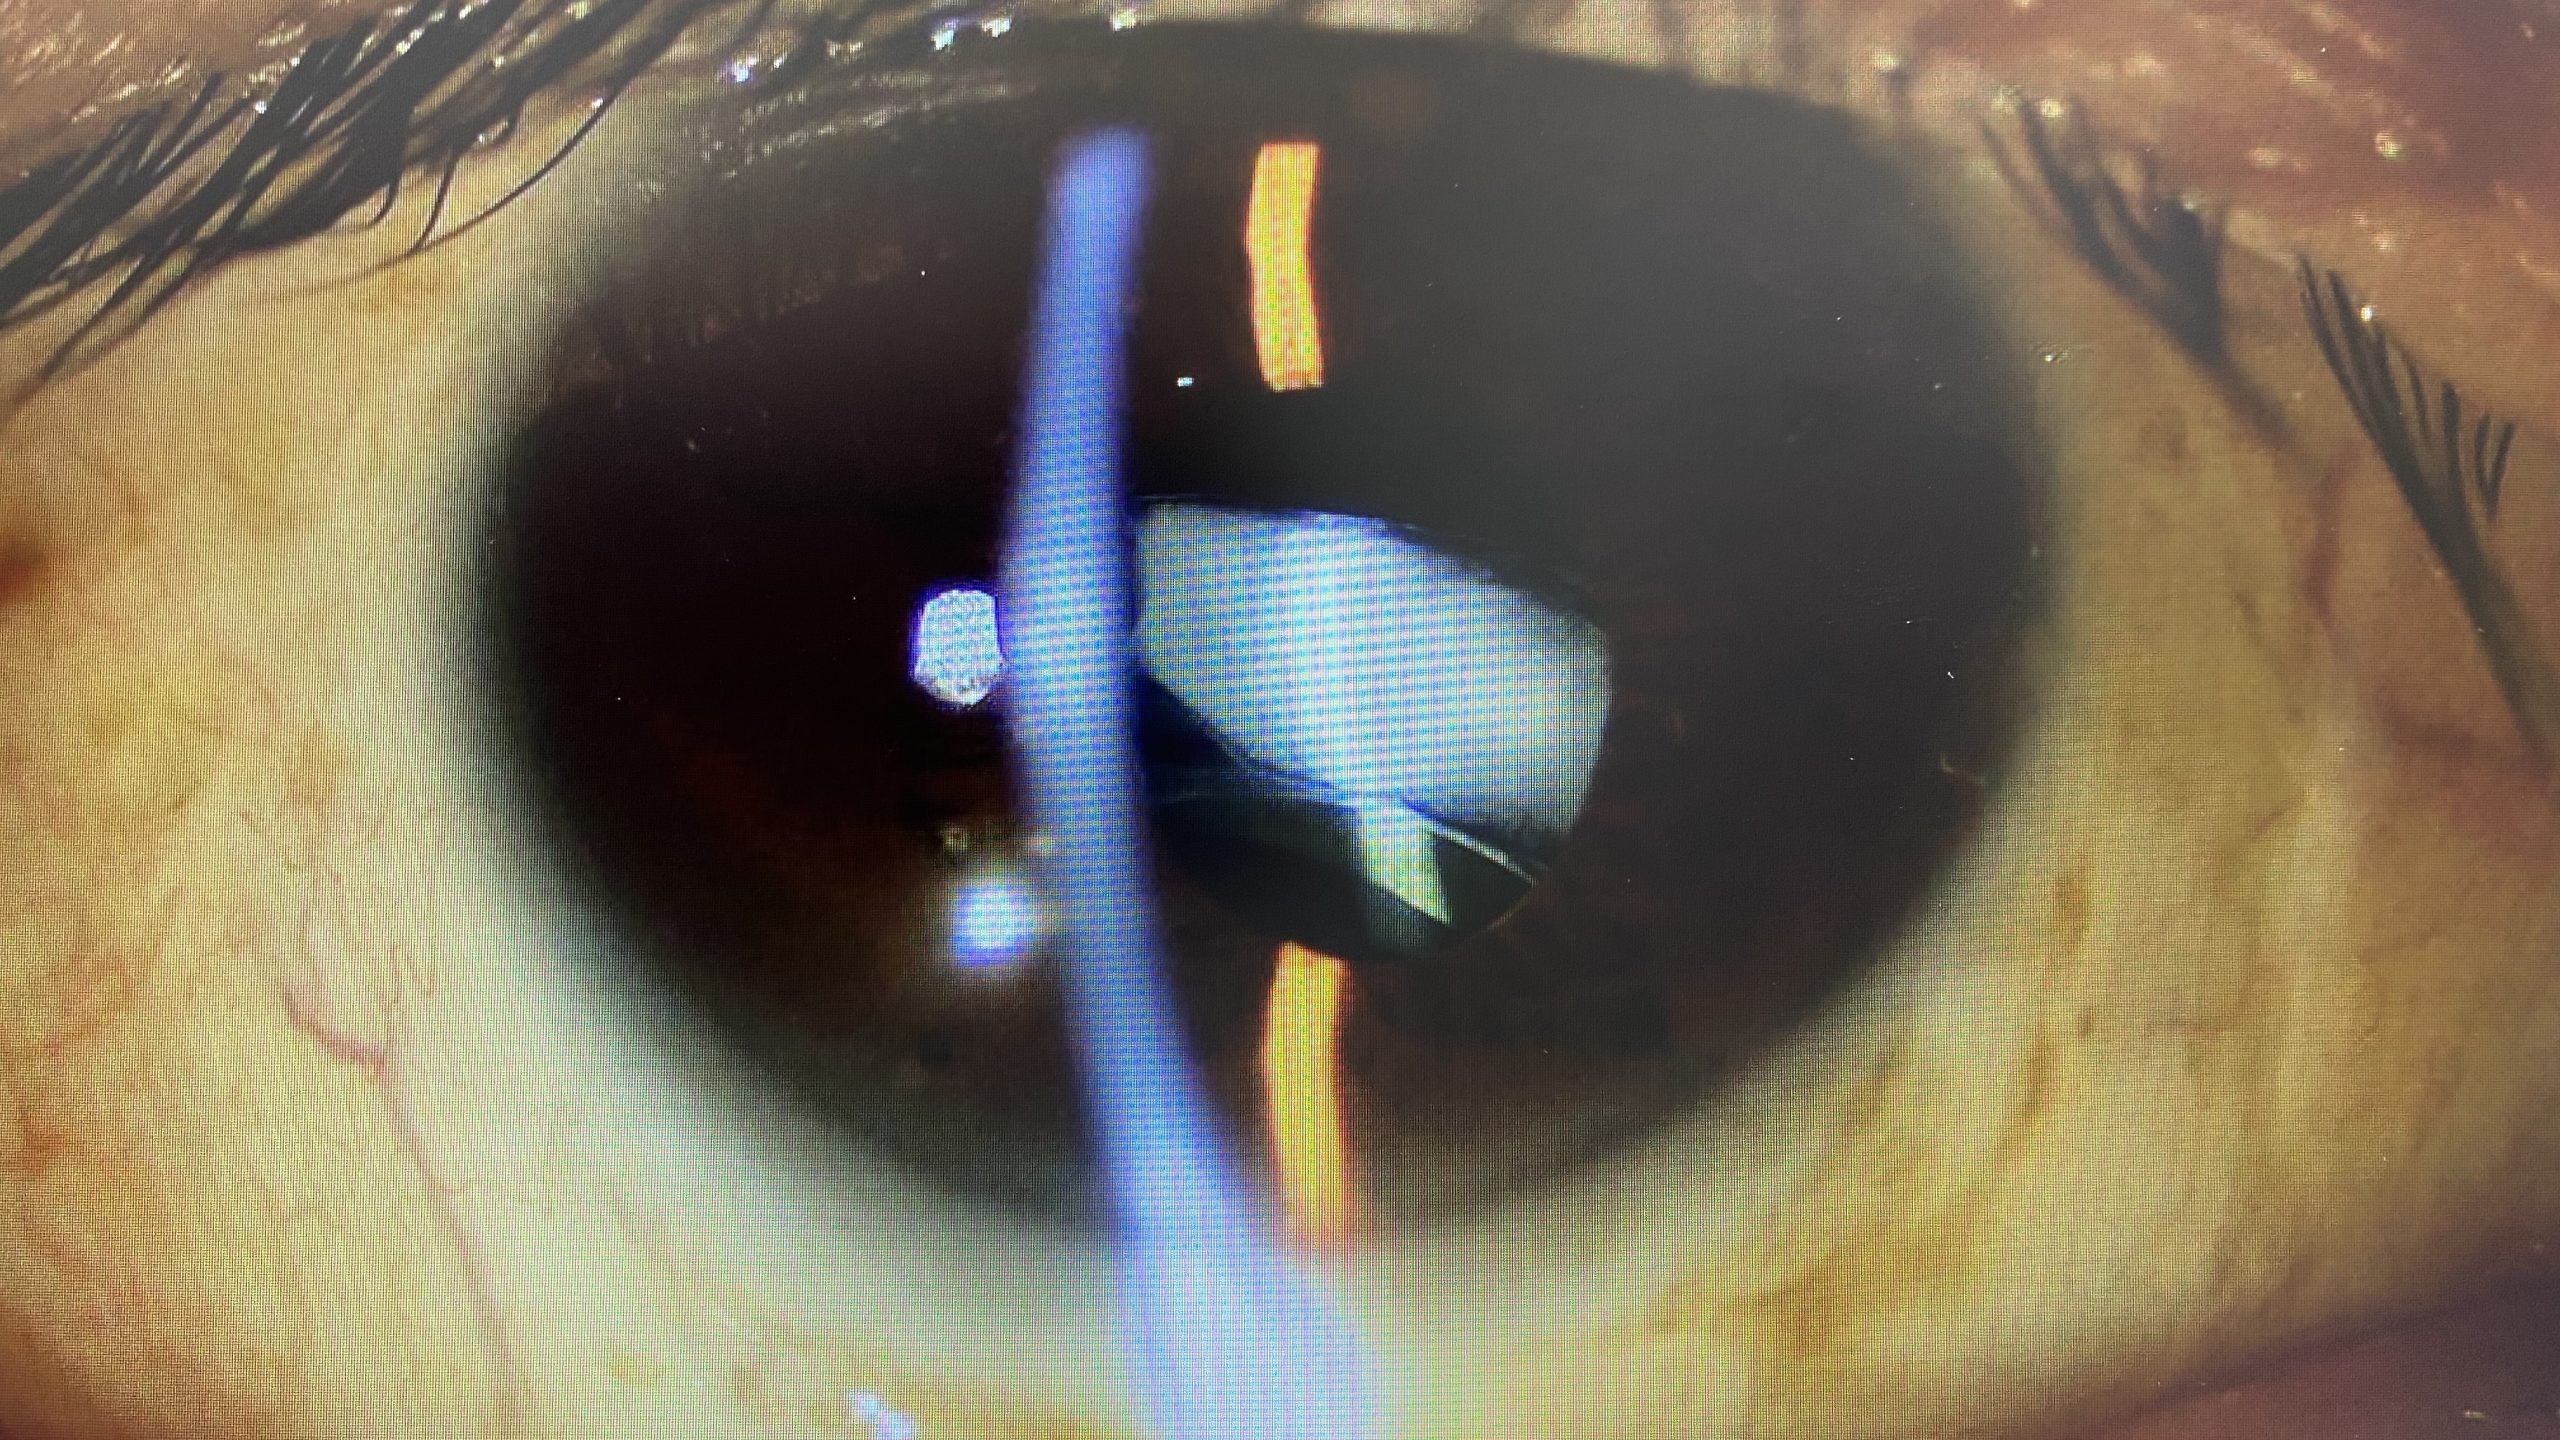

眼内レンズの直径は6mm ですが、柔らかい素材であるために折り畳んで目の中に挿入することができるので、2 ~ 3mm の傷口で手術を行うことができます。傷口が小さい方が、目に対して優しい手術になります。 白内障の手術